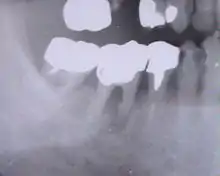

L'endodontie est la partie de l'odontologie qui traite de l'intérieur de la dent. Elle consiste dans la prévention, le diagnostic et le traitement des maladies de la pulpe dentaire et des infections péri-apicales (dans l'os autour des racines).

Le dentiste réalise le traitement endodontique (dévitalisation) d'une dent lorsque celle-ci ne peut plus être gardée vivante, soit parce qu'elle est déjà nécrosée, soit parce qu'elle risque de le devenir.

C'est l'ostéosclérose pulpo-périapicale qui a pour étiologie une pulpite chronique asymptomatique. Elle traduit l'hyperactivité du tissu osseux irrité. On peut la diagnostiquer radiographiquement (image périapicale radiodense). Elle disparaît lentement après un traitement canalaire adéquat.